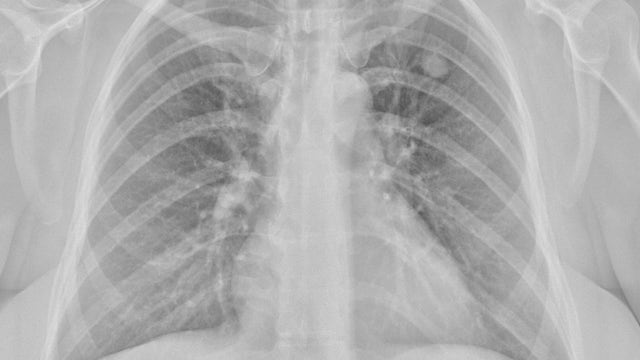

Arizona woman loses lung after ten-year battle with Valley fever symptoms: 'Thankful even to be alive'

Alexandra Soto was diagnosed with Valley fever ten years ago, and despite taking anti-fungal medications, she still suffered from long-term symptoms stemming from the disease.